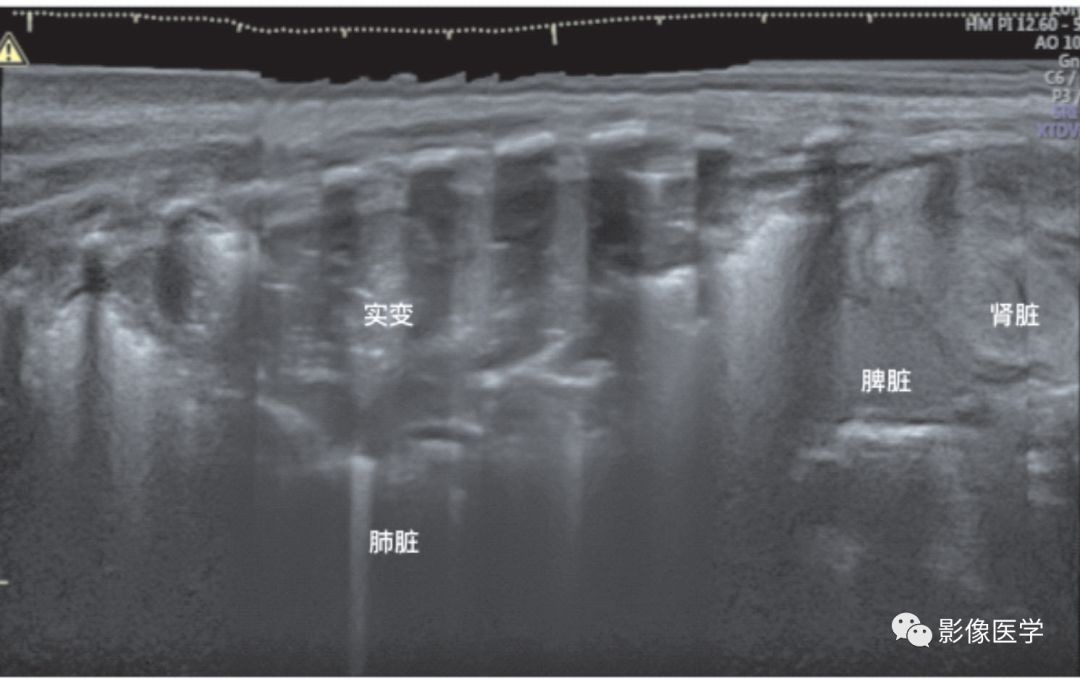

图6-30 肺炎的超声表现:宽景成像模式(2)

重症肺炎的超声表现(左侧肺炎)——宽景成像模式,依次显示肾脏、脾脏和肺脏。从超声影像上可以看出,左肺在每个肋间均见显著实变伴少许支气管充气征,每个肋间受累的程度不同。与图6-29相比,该患儿肺实变程度更重,严重受累部位(肺中野)已形成肺不张,肺组织含气量(支气管充气征)显著减少,提示病变程度较上例明显加重。此两例提示,宽景成像模式有助于了解全肺的病变情况。